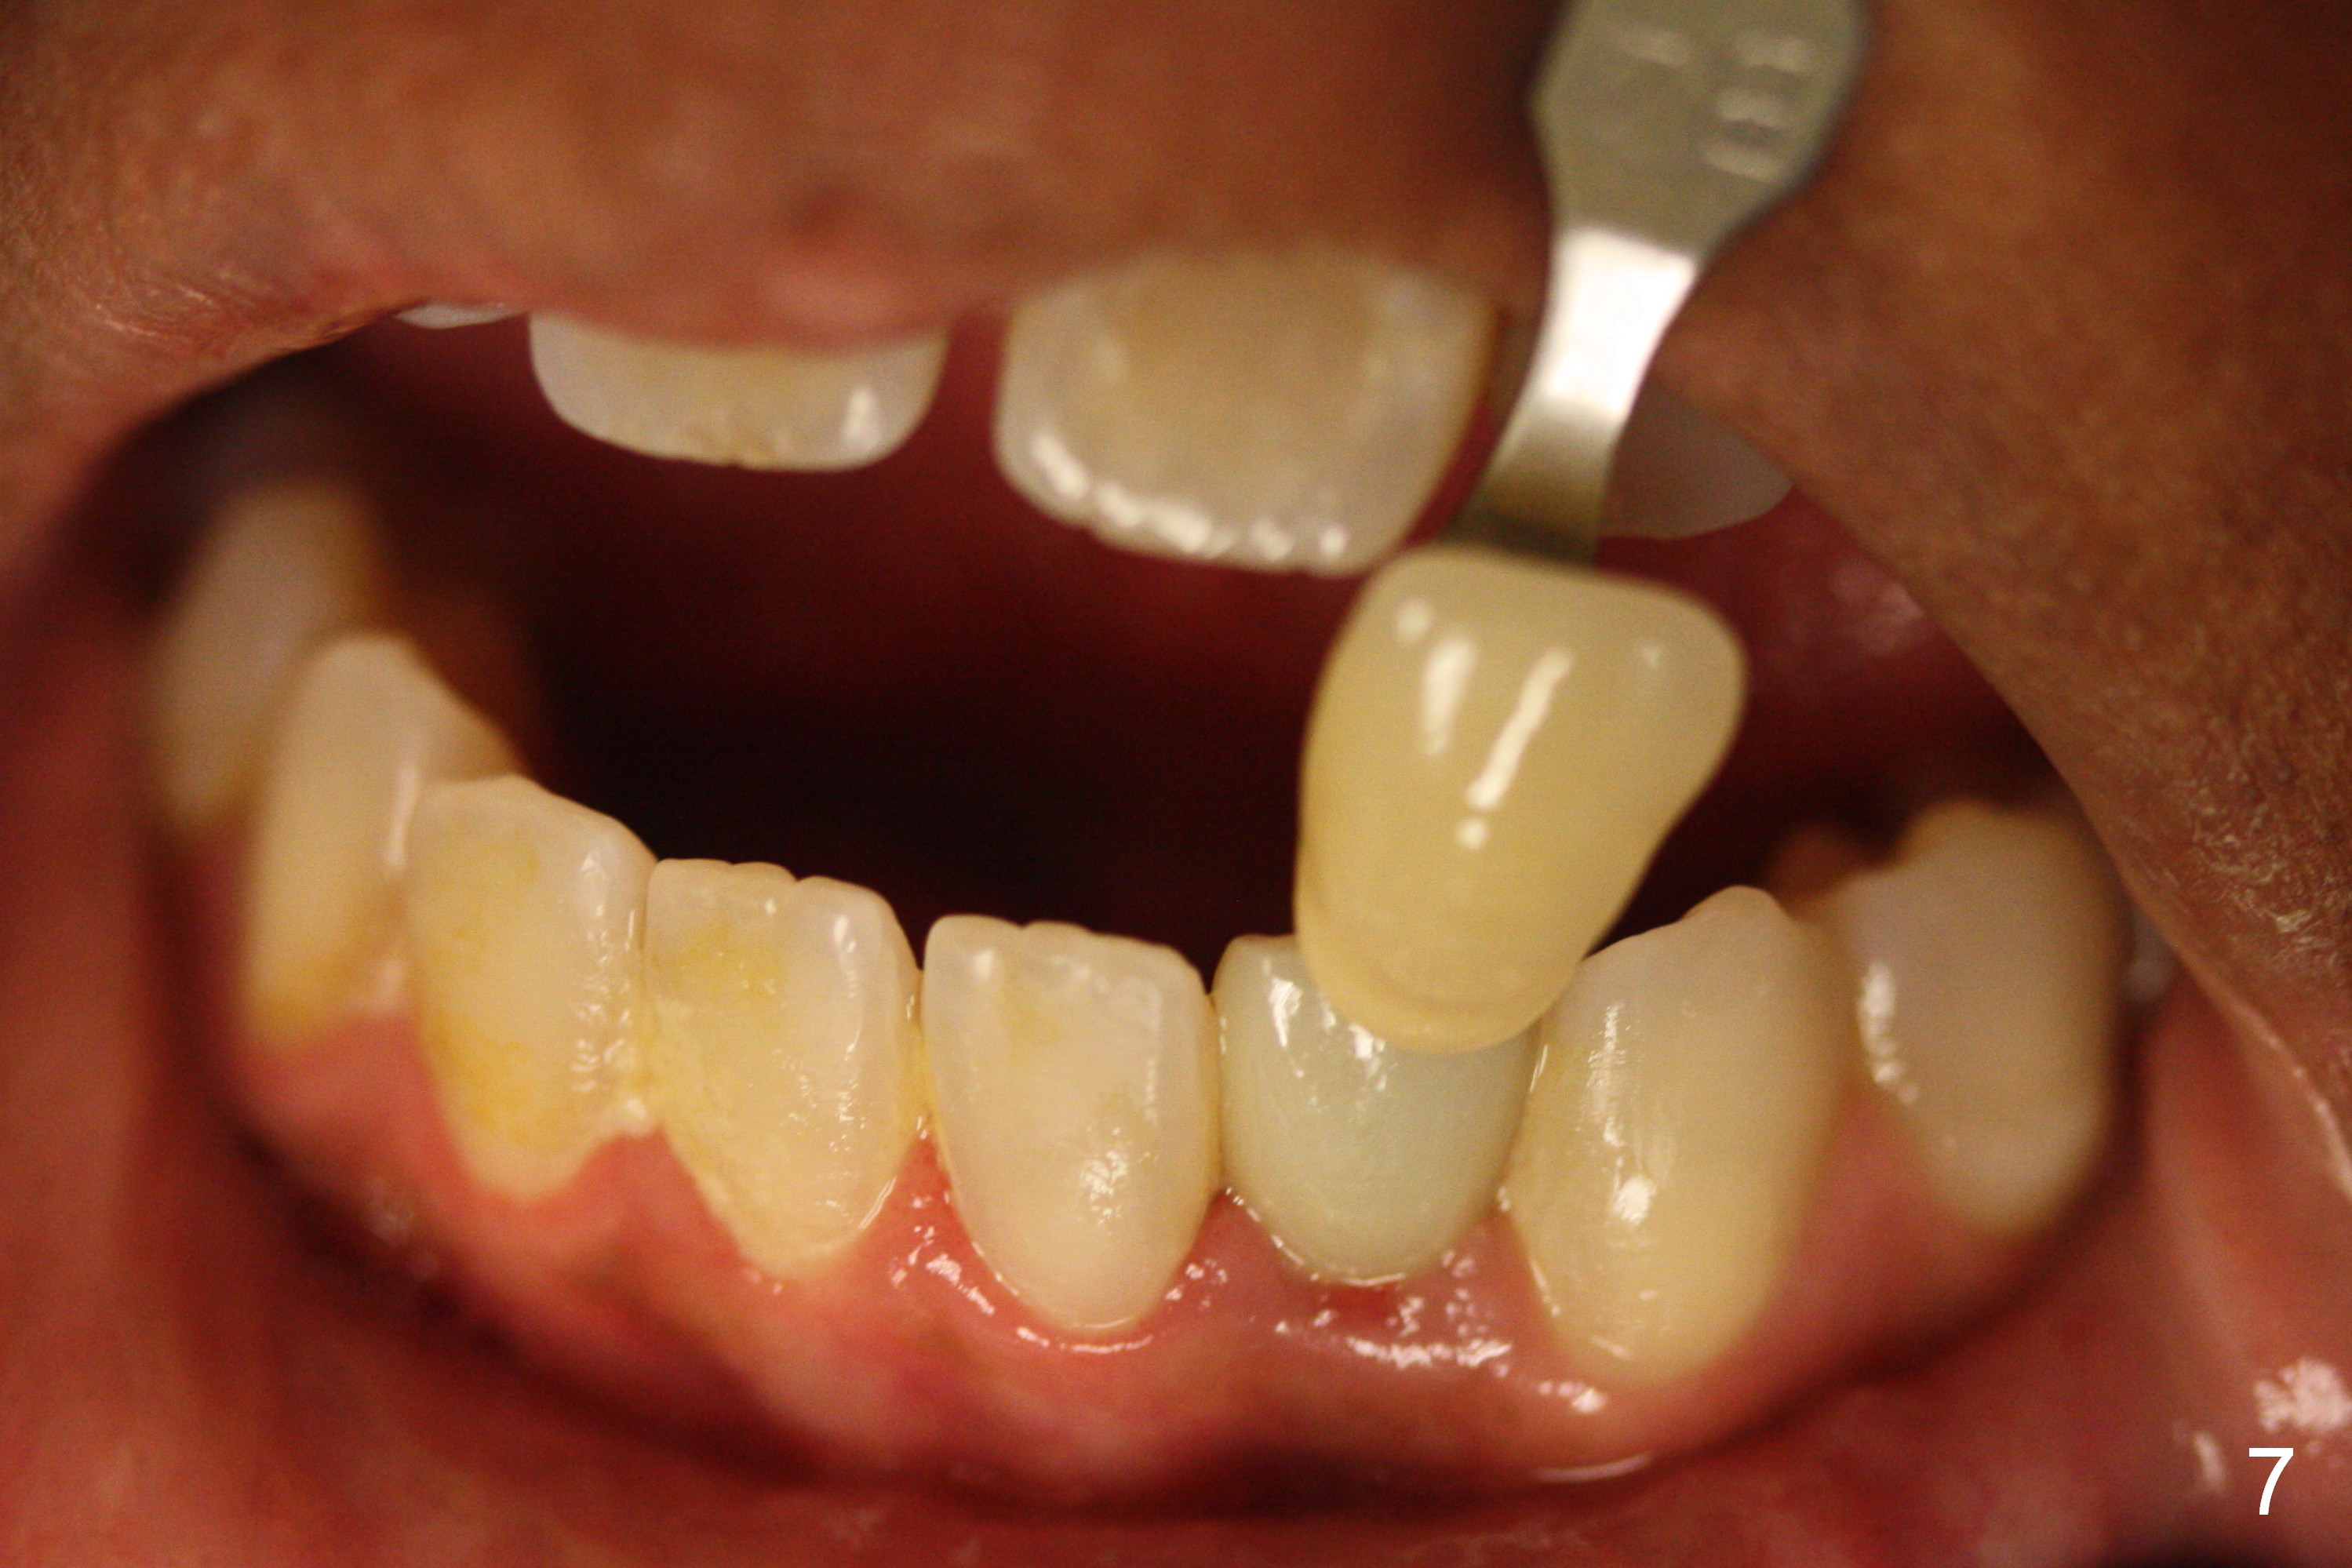

Choose a shade a little darker and more yellowish (Fig.4-7 before

cleaning; Fig.9-11 after cleaning). It

appears that there is a change in shade of crown over the time.

The patient is sure that the original shade was alright, but over the

time the shade changes. I wonder

whether it is due to stain/paint to the crown in the lab.